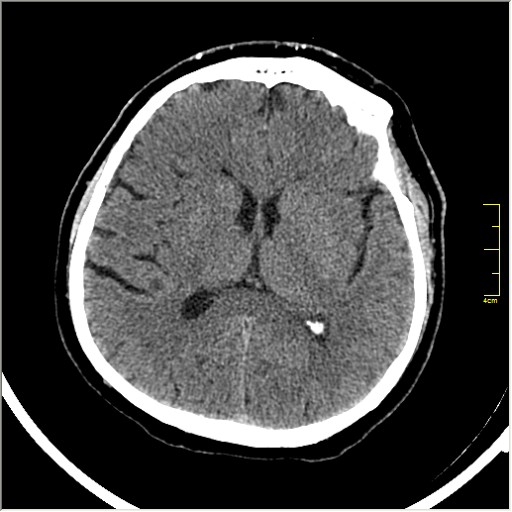

Пациентка Д. 64 года. Поступила с диагнозом ОНМК ???, жалобы на онемение и слабость в левой половине тела.

Ответ: Обратите внимание на правую среднемозговую артерию (MCA); М1 сегмент гиперденсен; сравните с другой стороной.

Этот признак называется [Dense MCA sign]; за счёт наличия тромбоза в её просвете. Этот признак является одним из ранних указующих КТ признаков при ишемическом инфаркте головного мозга. Более подробно об этом вы можете прочитать здесь: http://www.radiologyassistant.nl/en/483910a4b6f14.

Ну и для полноты картины, привожу контрольные КТ сканы выполненные через 24 часа: